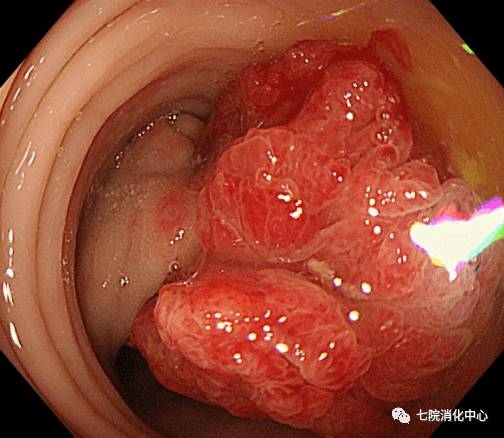

肚子不舒服 , 大便带血 , 排便习惯改变…… 65岁的王阿姨前段时出现的这些症状 可吓坏了她 , 于是来到西 安市胸科医院消化中心就诊 , 接诊的消化科副主任张蓉在了解其病情后 , 将其收治入院 。入院后肠镜检查发现 , 其肠道内多发大小不等息肉 , 最大直径1.8cm 。医生当即对息肉进行了切除处理 ,病理提示管状绒毛状腺瘤伴低级别上皮内瘤变—一种结肠癌的癌前期病变, 但庆幸的是发现较早 , 不然这个息肉很可能已经变成结肠癌 。目前王阿姨已经康复出院 , 之后只需要每半年复查一次肠镜 。